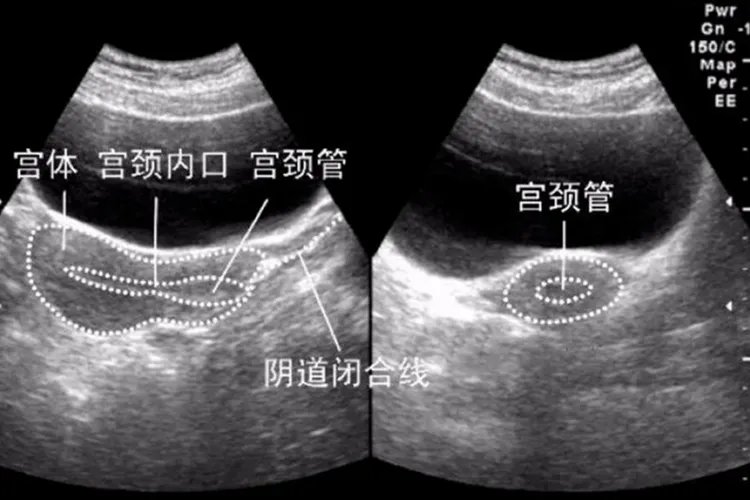

健康的子宫在做超声检查时可表现为边界清楚,表面光滑,内部呈中等强度回声,分布均匀。子宫横切面,呈三角形,体部呈椭圆形,中间为一短线状强回声。宫腔线状强回声周围为子宫内膜,内膜图像随月经周期而变化,增殖期(第6-14天)呈线样低回声,厚1-4mm。分泌期(第15-20天),内膜继续增厚达5-10mm,呈强回声,月经期第1-5天,因子宫内膜功能破坏,回声模糊不清。